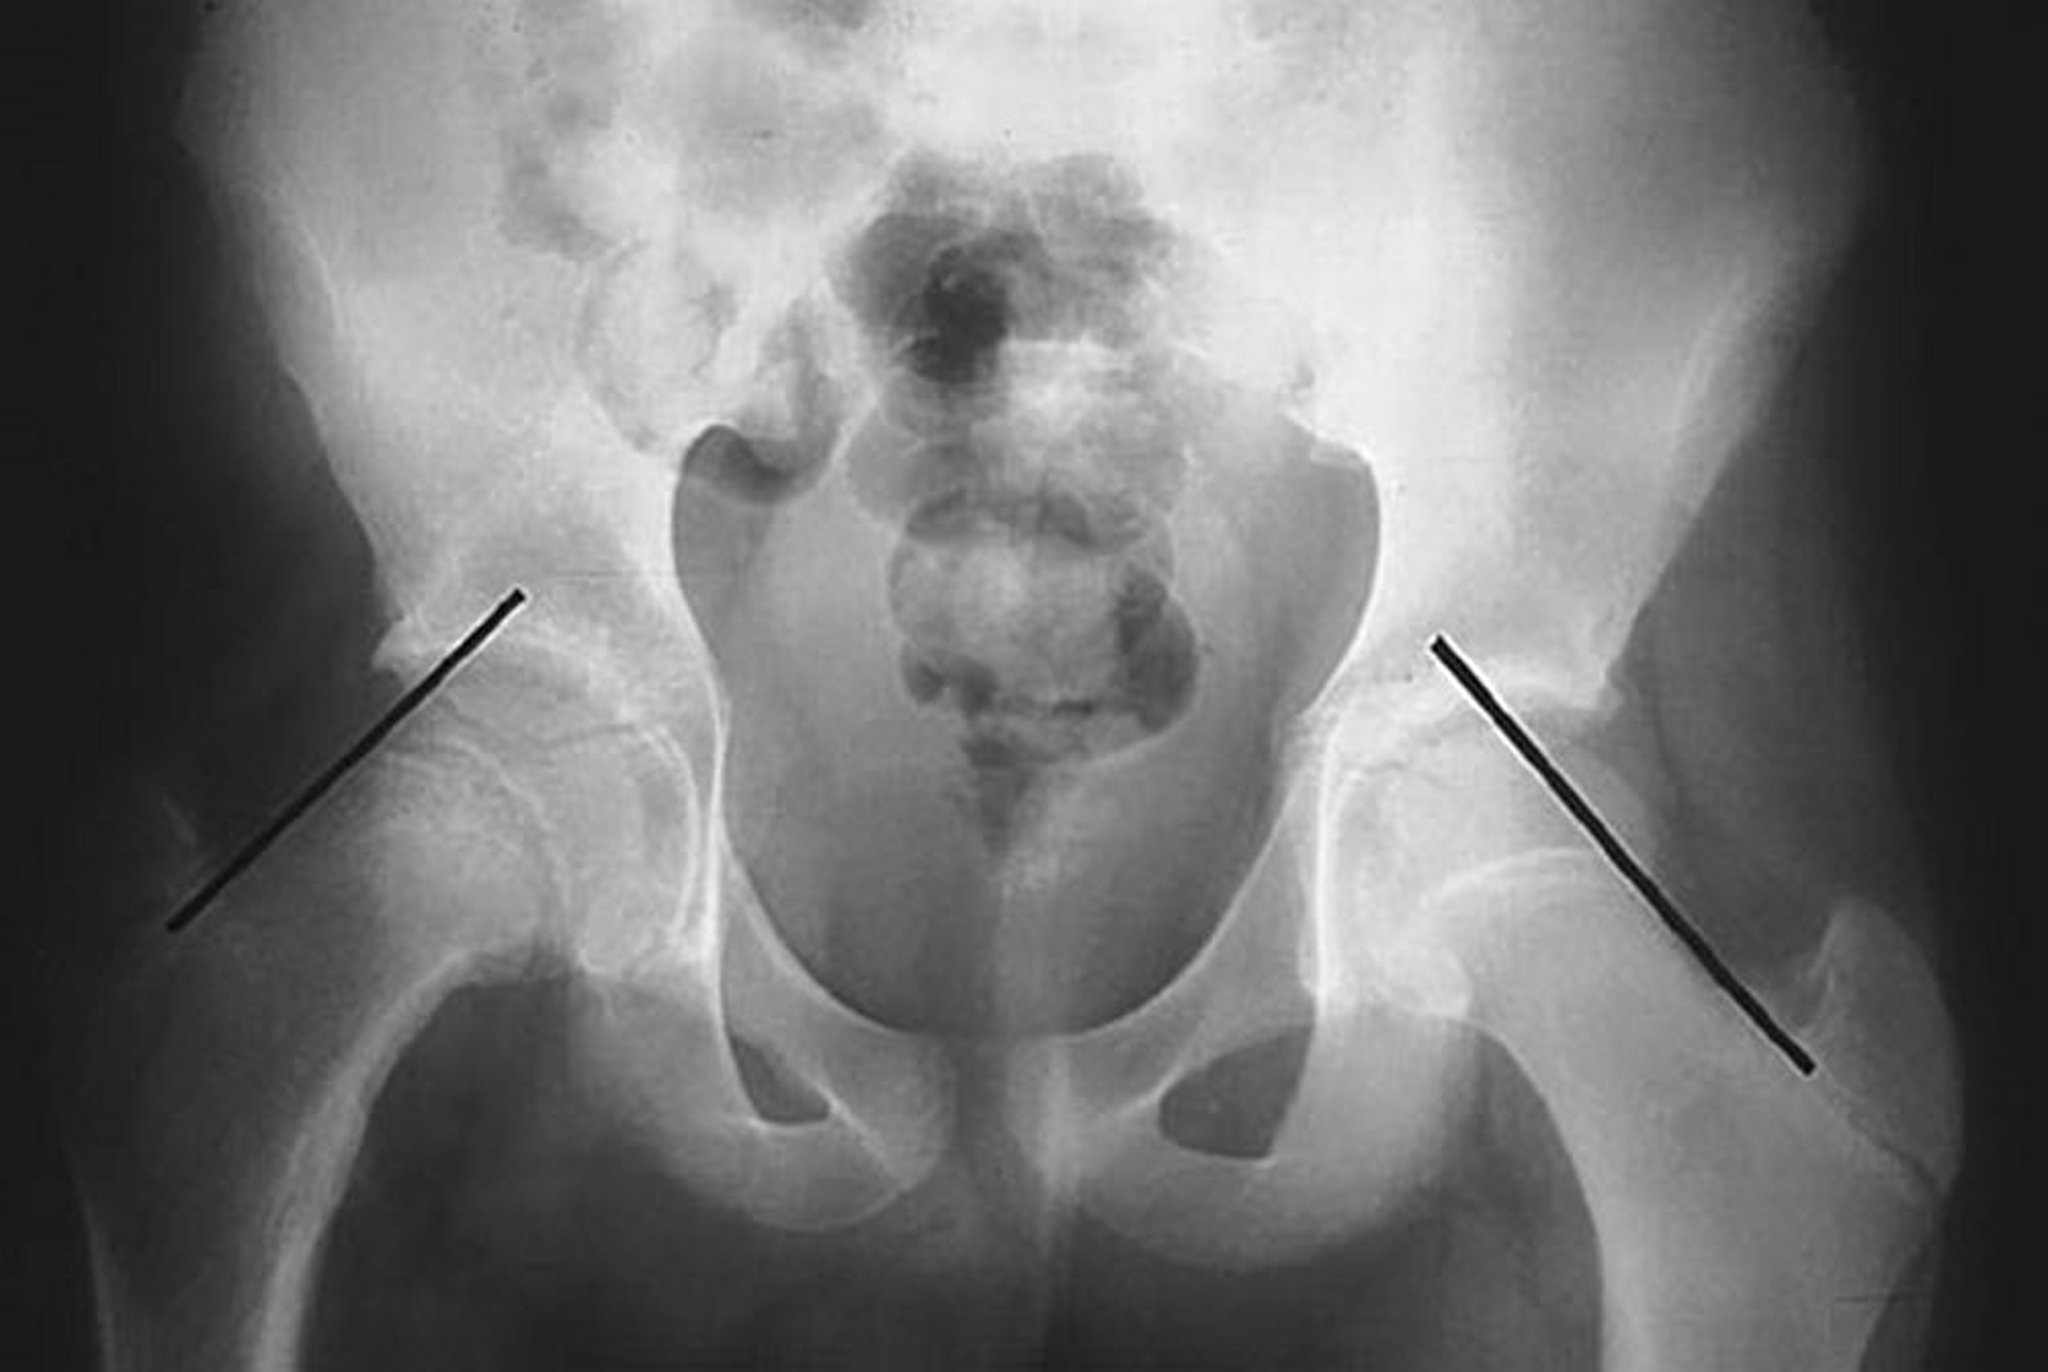

Bei diesem Patienten mit verrutschter Kapital-Schenkel-Epiphyse (SCFE) der rechten Hüfte werden kleine Linien an der oberen Grenze des Oberschenkelhalses gezogen. Beachten Sie, dass sich der Femurkopf auf der betroffenen rechten Seite unterhalb der Klein-Linie befindet, während sich ein erheblicher Teil des Femurkopfs auf der linken Seite nicht auf der Klein-Linie befindet.

By permission of the publisher. From Campbell R Jr: Current Orthopedic Diagnosis and Treatment. Herausgegeben von J.D. Heckman, R.C. Schenck und A. Agarwal. Philadelphia, Current Medicine, 2002.